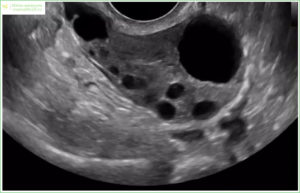

- УЗИ: наличие одного или нескольких доминантных фолликулов в яичнике, диаметр которых составляет 17-20 мм, а также отсутствие желтого тела яичника и жидкости в ретроутеральном пространстве;

Мультифолликулярные яичники, сокращенно МФЯ, — это диагноз, который ставят, если на УЗИ обнаружено более восьми фолликулов. Большое количество фолликулов в яичниках не считается болезнью, особенно если овуляция происходит.

- УЗИ может определить увеличенный фолликул;

Определяется данная патология посредством УЗИ. Может потребоваться допплерография для изучения кровотока в сосудах фолликулярных стенок. Если он невелик, это может указывать на развитие персистенции.